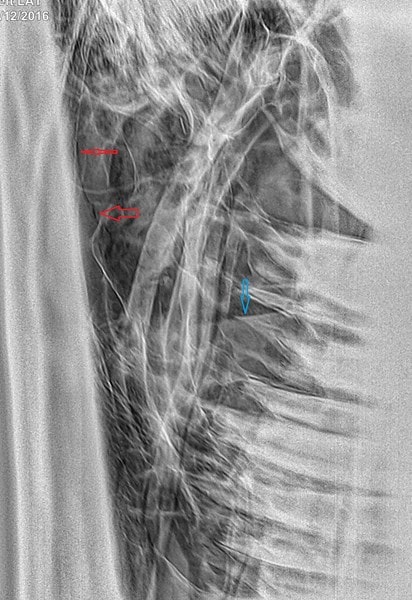

Radiographs were taken, the teeth look OK and there are various fluid lines within the sinuses from the blood (second photo: blue arrows are fluid lines and red arrows are at either end of a fracture line).